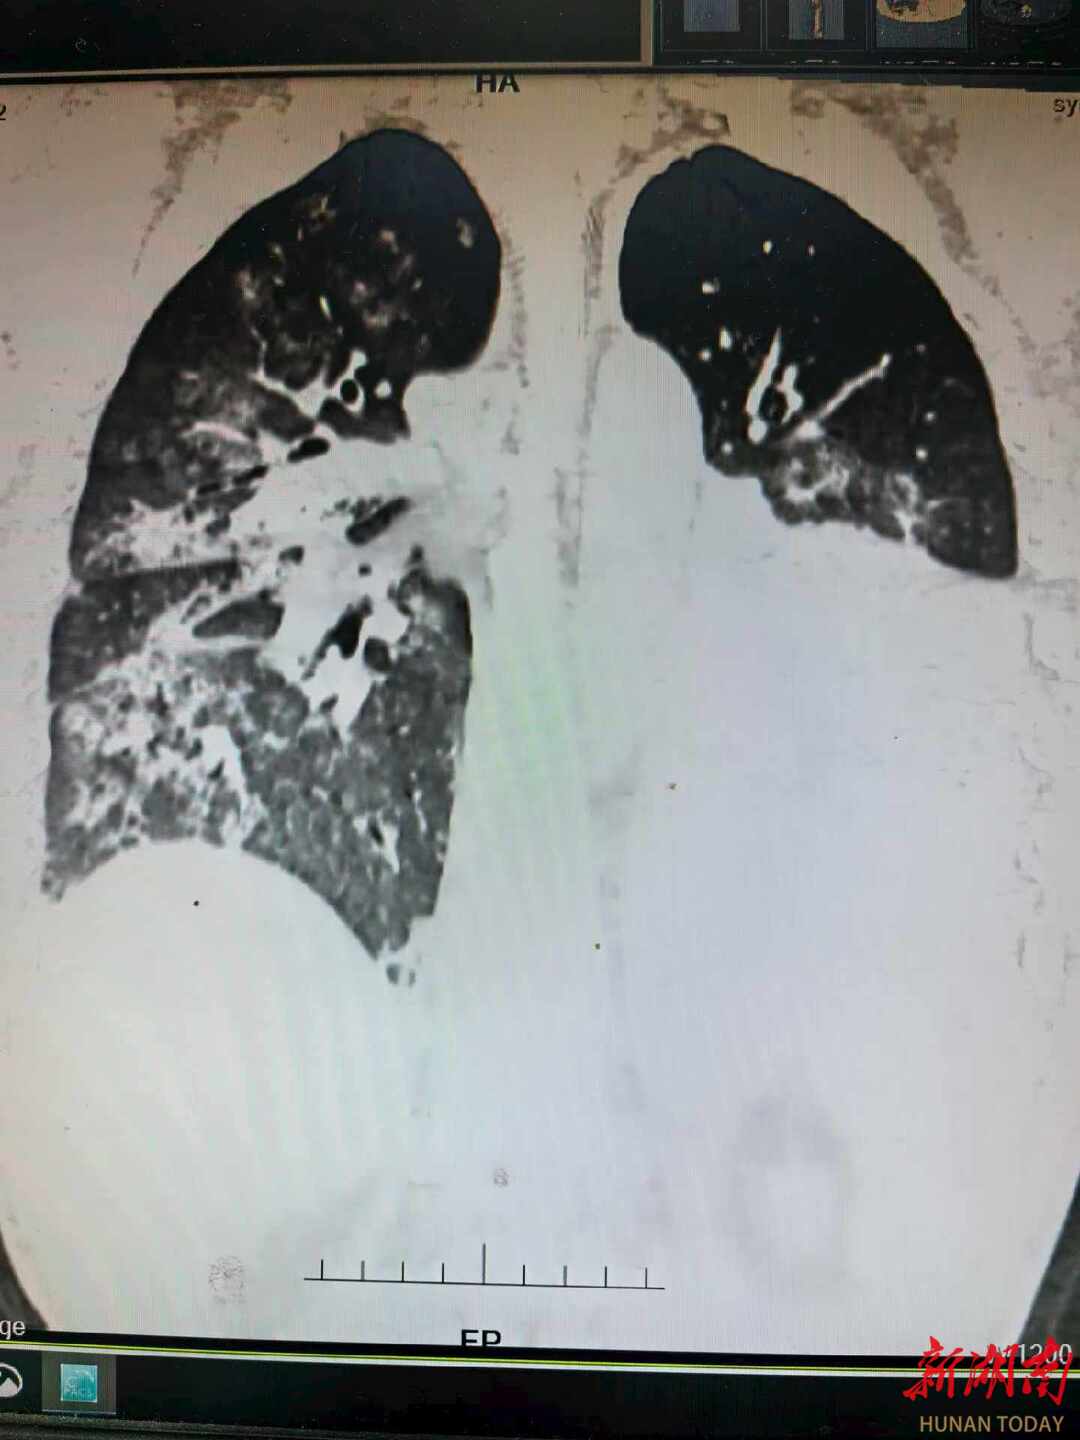

患者肺部CT影像

据介绍,该患者在感染肺炎克雷伯菌后,迅速发展为重症肺炎、脓毒性休克和呼吸衰竭,再到肺脓肿、支气管胸膜瘘、消化道大出血……形势极为惊险。尽管患者及时就地求医,但入院短短数小时便发展为脓毒性休克和呼吸衰竭,随后患者被迅速转入湘雅医院急诊科。

转至湘雅医院后,患者的肺功能已近崩溃,常规呼吸机已经难以维持生命体征。抢救团队当机立断,为男子启动了VV-ECMO(体外膜肺氧合),用这台“人工肺”替代衰竭的肺,为后续抢救争取宝贵时间。祸不单行,在ECMO治疗期间,男子出现了急性肾功能衰竭,不得不依赖持续的血液净化治疗。同时,用于防止ECMO管路内凝血的抗凝药物,竟诱发了一种棘手的并发症——肝素诱导的血小板减少症(HIT)。

在后续CT检查中,医生发现其左肺形成了肺脓肿,并且发生了支气管胸膜瘘。这意味着感染灶持续存在,像一个“定时炸弹”。经过多学科团队的慎重评估,最终为患者实施了左下肺叶切除术。当感染的核心被切除,这场持久战终于迎来了转折点。术后约一周,患者即出院返回老家。据随访,患者复查肺部CT显示恢复良好。